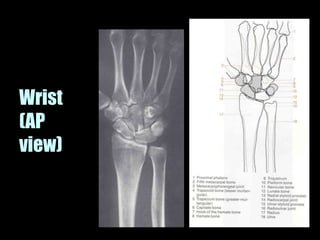

This document provides an overview of normal musculoskeletal imaging. It discusses basic x-ray concepts and densities. It then reviews normal anatomy as seen on x-rays of the skull, spine, pelvis, chest, and extremities. Key anatomical structures are labeled on example x-rays for the shoulder, hip, knee, and foot. Quizzes are included to test recognition of anatomical structures and patient age based on x-rays.